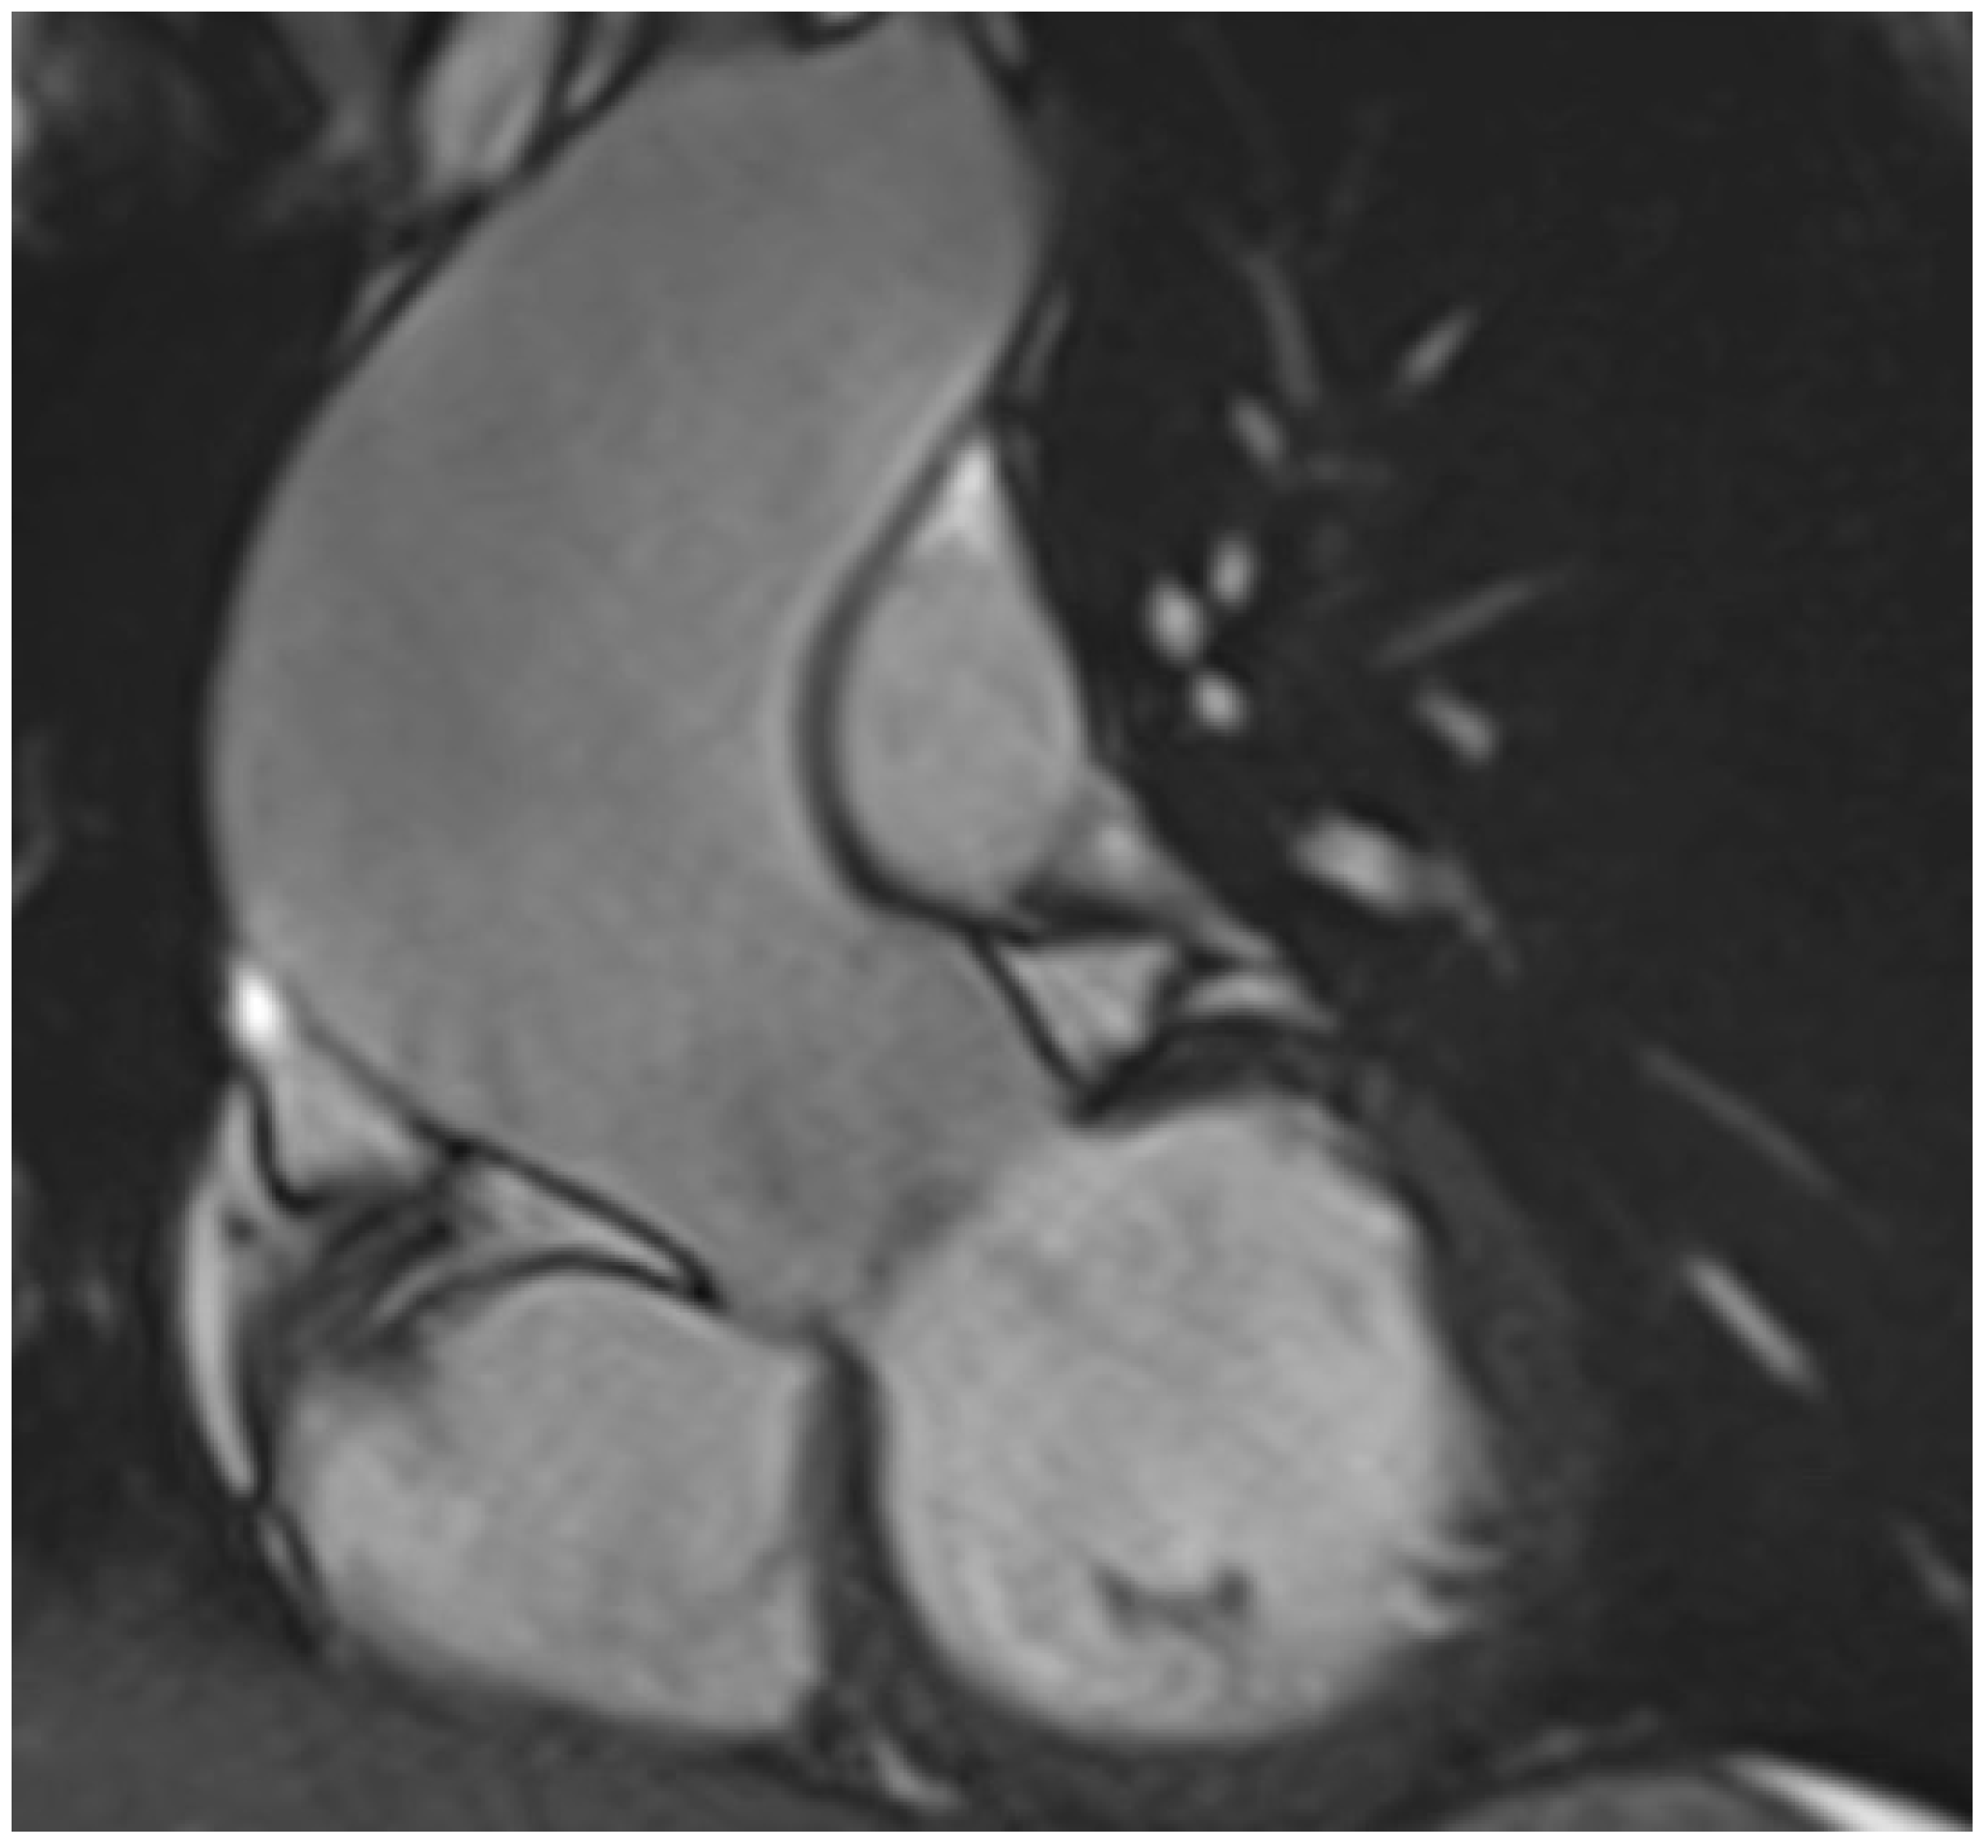

5. Diagnostic Imaging